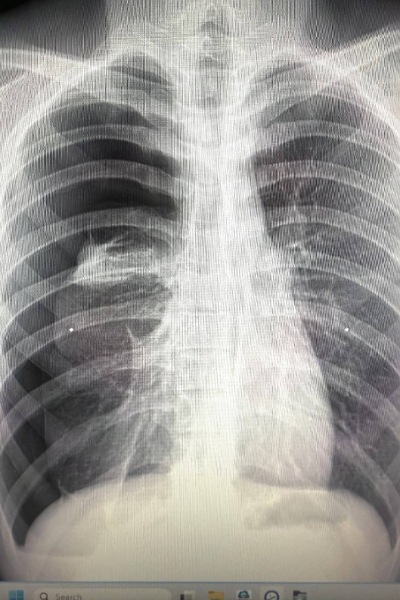

เมื่อไม่นานมานี้ ผมได้เจอเคสผู้ป่วยหญิงอายุราว 40 ปี มารักษาด้วยอาการเจ็บแน่นหน้าอก เป็น ๆ หาย ๆ อยู่หลายครั้ง แต่ไม่รู้สึกเหนื่อย รู้สึกว่าเมื่อมีอาการเจ็บหน้าอกทุกครั้ง มักจะเป็นในช่วงขณะมีประจำเดือน จึงมีอยู่ช่วงหนึ่งมีอาการเจ็บหน้าอกมากจึงรีบมาพบแพทย์ที่โรงพยาบาล หลังจากการตรวจสอบเอกซเรย์ พบว่าเป็นโรคลมรั่วในเยื่อหุ้มปอด ซึ่งมีโอกาสเสียชีวิตสูงหากไม่ทำการรักษา จึงรีบรับการรักษาตัวเข้าโรงพยาบาล

รศ.นพ.ศิระ เลาหทัย แพทย์ผู้เชี่ยวชาญศัลยศาสตร์ ทรวงอกเฉพาะทางด้านการผ่าตัดส่องกล้องในช่องทรวงอก โรงพยาบาลวชิรพยาบาล กล่าวว่าจากการวินิจฉัย ส่วนมากการทำ X-Ray หรือ ทำเอกซเรย์คอมพิวเตอร์ (CT Chest) หรือ MRI อาจพบได้ แต่อย่างไรก็ตามยังไม่มีการตรวจใดมีประสิทธิภาพที่สามารถวินิจฉัยโรคนี้ได้โดยตรง โดยในบางรายอาจพบถุงลมบริเวณยอดของปอดร่วมด้วยได้ (Lung Bleb) ในส่วนของการรักษาในโรคลมรั่วในเยื่อหุ้มปอดนี้ ประกอบด้วย 2 อย่าง ได้แก่1)การรักษาด้วยการผ่าตัด(ส่องกล้อง) และ2)การรักษาด้วยยา